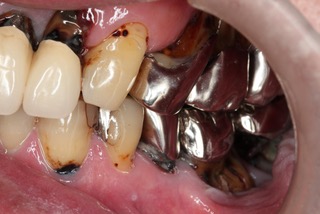

右側 before